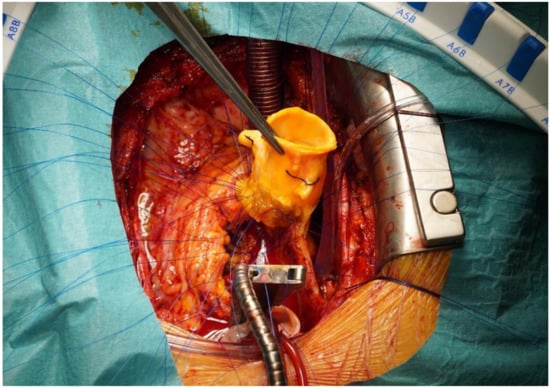

3.3. Surgical Management

| Time from diagnosis to redo surgery (months) | 3.6 (2.7–4.2) |

| Substitute | |

| Aortic homograft | 6 (86) |

| Bovine pericardial tube | 2 (28) |

| Annuloplasty ring and Gore-Tex neo-chordae | 1 (14) |

| Median CPB time (min) | 161 (149–168) |

| Median aortic cross-clamp time (min) | 141 (128–182) |

| Postoperative bleeding | 4 (57) |

| Positive explant cultures | 7 (100) |

| Median hospital length of stay (days) | 16 (11–24) |